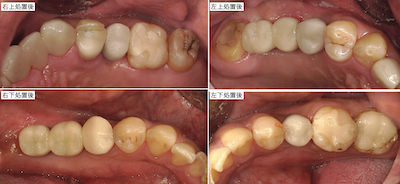

上部構造装着後です。

各々の部分の比較です。まず右上です。

左上です。

左下です。

右下です。